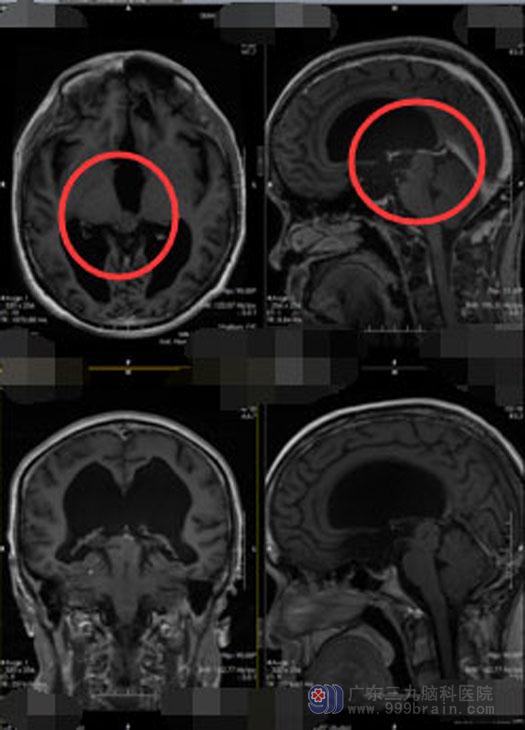

黄大哥害怕了,今年在家人的陪伴下,他再次走进了广东三九脑科医院神经外五科。黄大哥告诉医生:这两年他看过不少的医生,也从不同的渠道了解了一些疾病的知识,很多医院都不肯给他做手术,受了很多苦,感觉自己像个废人,这次下定了决心,无论有多大风险,自己都能接受。复查脑部MR提示:松果体区占位性病变,左侧额叶底部软化灶形成,幕上梗阻性脑积水(重度),左组鼻旁窦炎症。

术后三天复查头部MR:原病变已切除,垂体、小脑及脑干未见明显异常,所见范围内鼻咽部未见异常信号影。病理检验结果:松果体区低级别神经上皮细胞肿瘤,脑干背侧节细胞胶质瘤。术后第五天,黄大哥生命体征平稳、对答正确、四肢活动自如,视力视野正常,听力正常,未再出现脑脊液鼻漏情况。